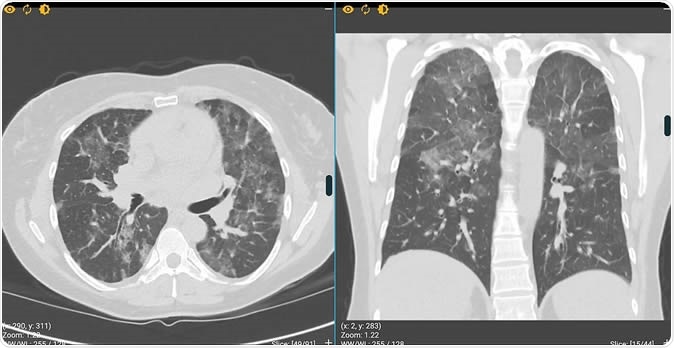

Free virtual clinical environment that helps clinicians to become better at recognising the early CT signs of COVID-19. Image Credit: DetectEd

Describing the tool, program co-creator Stuart Grieve says that COVID-19 shows up in CT scans of the lungs in three ways, mainly. The first thing the doctor must do is ask for a history of risk. If this is positive, the earliest CT finding of infection is the “ground-glass opacity,” where the lung looks like the view from a frosted window rather than the transparent black of the normal lung.

The second sign is termed “crazy paving” and denotes a more advanced form of the disease – patches of the lung turn white, with no obvious pattern to them. And the third is a sign of severe lung disease, with consolidation of the lung – the lung is filled with mucus and looks white because there is no air within the lung in that field.